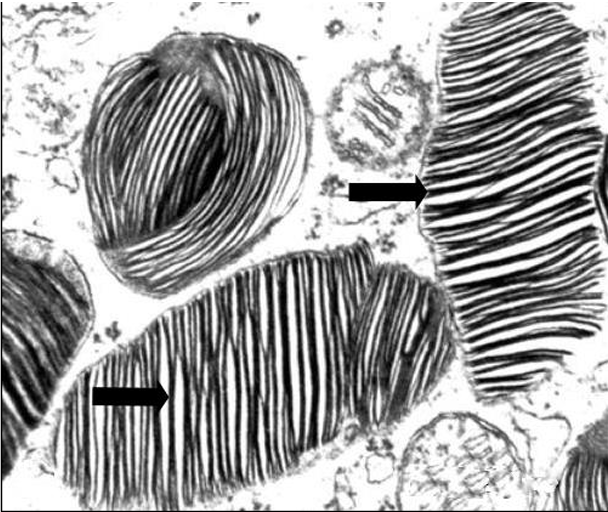

Transmission electron micrograph of spinal cord from a Humboldt penguin

What are the structures denoted by the arrows?

Myelin figures.